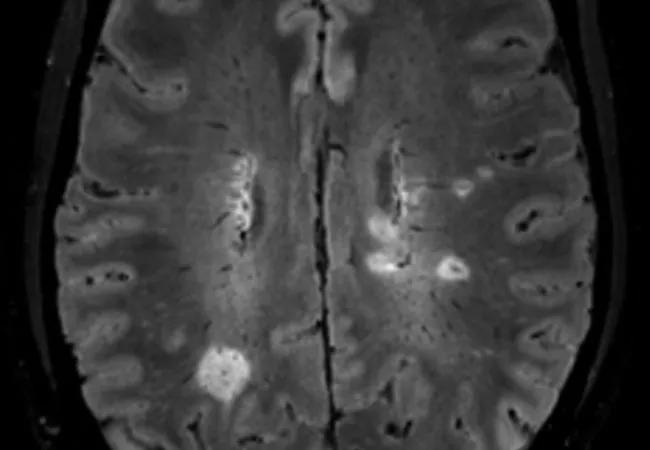

brain MRI showing central vein sign

The CVS refers to a vein visualized inside a white matter lesion on T2* MRI sequences that appears as a hypointensity relative to the surrounding lesion. “The presence and pathophysiologic significance of a central vein in MS white matter lesions has been extensively described in both pathology- and MRI-based studies,” notes Dr. Ontaneda.

Patients will be enrolled when presenting to an MS center for diagnostic referral, and they will undergo follow-up at prespecified intervals for 24 months. Brain MRI will be performed at baseline and 24 months, with scans scored on the basis of CVS criteria. T2-weighted fluid-attenuated inversion recovery (FLAIR) imaging will be combined with T2*-weighted segmented echo-planar imaging to enable simultaneous identification of white matter lesions and venous structures (Figure).

Figure. Representative central vein images in a research participant with multiple sclerosis. Hyperintense lesions are demonstrated on T2-FLAIR images shown in axial (A), sagittal (B) and coronal (C) views. Central veins are observed in a preponderance of lesions in the merged FLAIR and T2*-weighted images shown in axial (D), sagittal (E) and coronal (F) views.